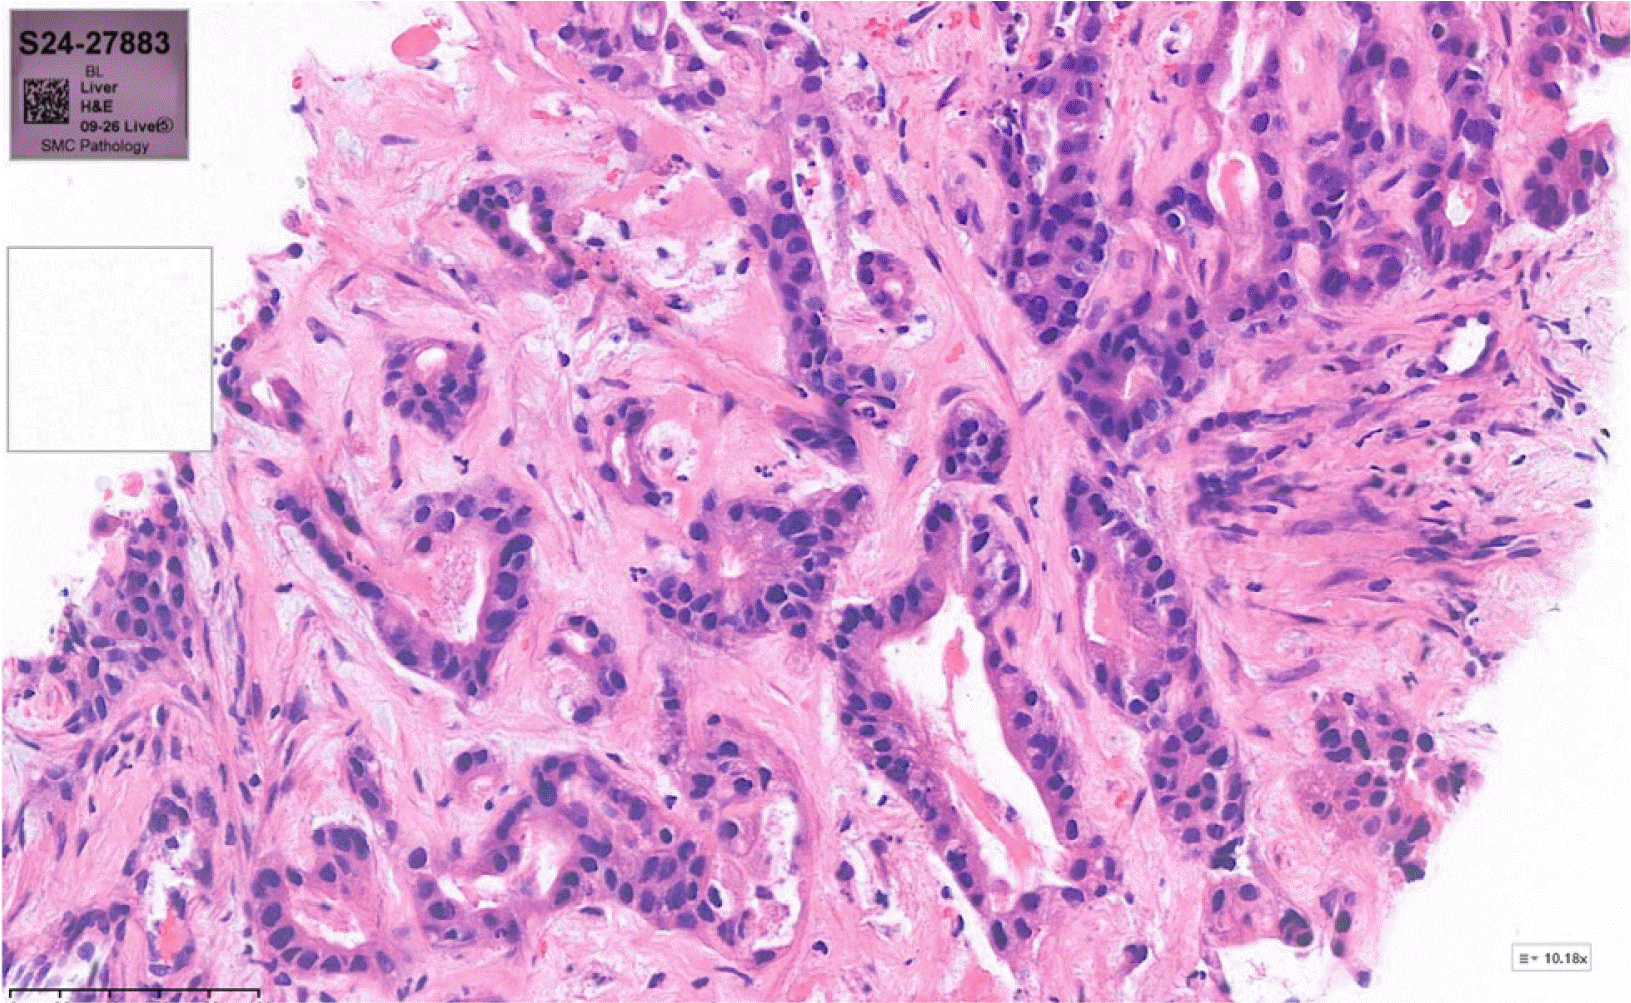

Fig. 5

Liver biopsy showing moderately differentiated adenocarcinoma with tumor necrosis (H&E stain, ×200).

Initially, empirical antibiotic treatment with moxifloxacin was started, and percutaneous catheter drainage (PCD) was performed to manage the suspected liver abscess. The drainage fluid was yellowish and turbid, with the analysis showing a white blood cell count exceeding 100,000 cells/mm³ with 97% polymorphonuclear neutrophils, a protein level of 1,490 mg/dL, an albumin concentration of 940 mg/dL, and a CEA level of 10,600 ng/mL. The cytology of the fluid revealed a few atypical cells, but subsequent evaluations were negative for malignant cells (Fig. 4). The entamoeba histolytica IgG serology was negative. No growth was observed in cultures. A liver biopsy performed six days after sufficient drainage revealed a moderately differentiated adenocarcinoma with tumor necrosis, leading to the final diagnosis of primary cholangiocarcinoma (Fig. 5). Positron emission tomography-computed tomography revealed hypermetabolic lesions in segment 4 and the right internal mammary nodal chain (Fig. 6). A biliary CT was performed 22 days after inserting the PCD, which showed that the abscess had collapsed compared to previous imaging. On the other hand, the lesion suspected to be cholangiocarcinoma showed no significant change (Fig. 7). The PCD output remained consistently brown-yellowish, with daily volumes ranging from 100 to 150 cc since its insertion, and never decreased below 50 cc. The drainage characteristics were not thick or pus-like, and the output remained stable despite being drained for more than 21 days, which reduced the likelihood of a liver abscess. Consequently, the catheter was maintained in situ. Nevertheless, the drainage volume remained above a certain level, so the patient continued the drainage while initiating systemic chemotherapy.